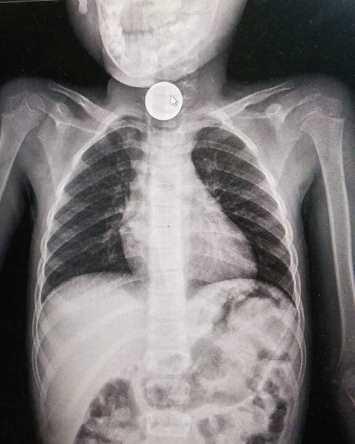

وأوضح رئيس دائرة الأطفال بمستشفى الملكة رانيا العبدالله العميد الطبيب عبدالله غنما، أن إبتلاع الأجسام الغريبة مشكلة شائعة لدى الأطفال خصوصاً من عمر عام لعشرة اعوام، وأضاف أن تم إزالة انواع مختلفة من الأجسام الغريبة من جسم الأطفال مثل العملات المعدنية والكرات الزجاجية وبعض الأجسام الحادة وبطاريات الالعاب.

وبين العقيد الروله بأن الأجسام الغربية تمثل خطراً على حياة الطفل لما تسببه من مضاعفات خطيرة، فقد تؤدي لتضيق بالمرئ أوعمل ثقب بالمرئ من خلال بطاريات الألعاب المبتلعه، أضافه لانسداد بالأمعاء من خلال العملات المعدنية، وأضاف الروله ان العمليات اجريت بمشاركة المقدم الطبيب محمد الشطناوي، والرائد الطبيب محمد القرعان.